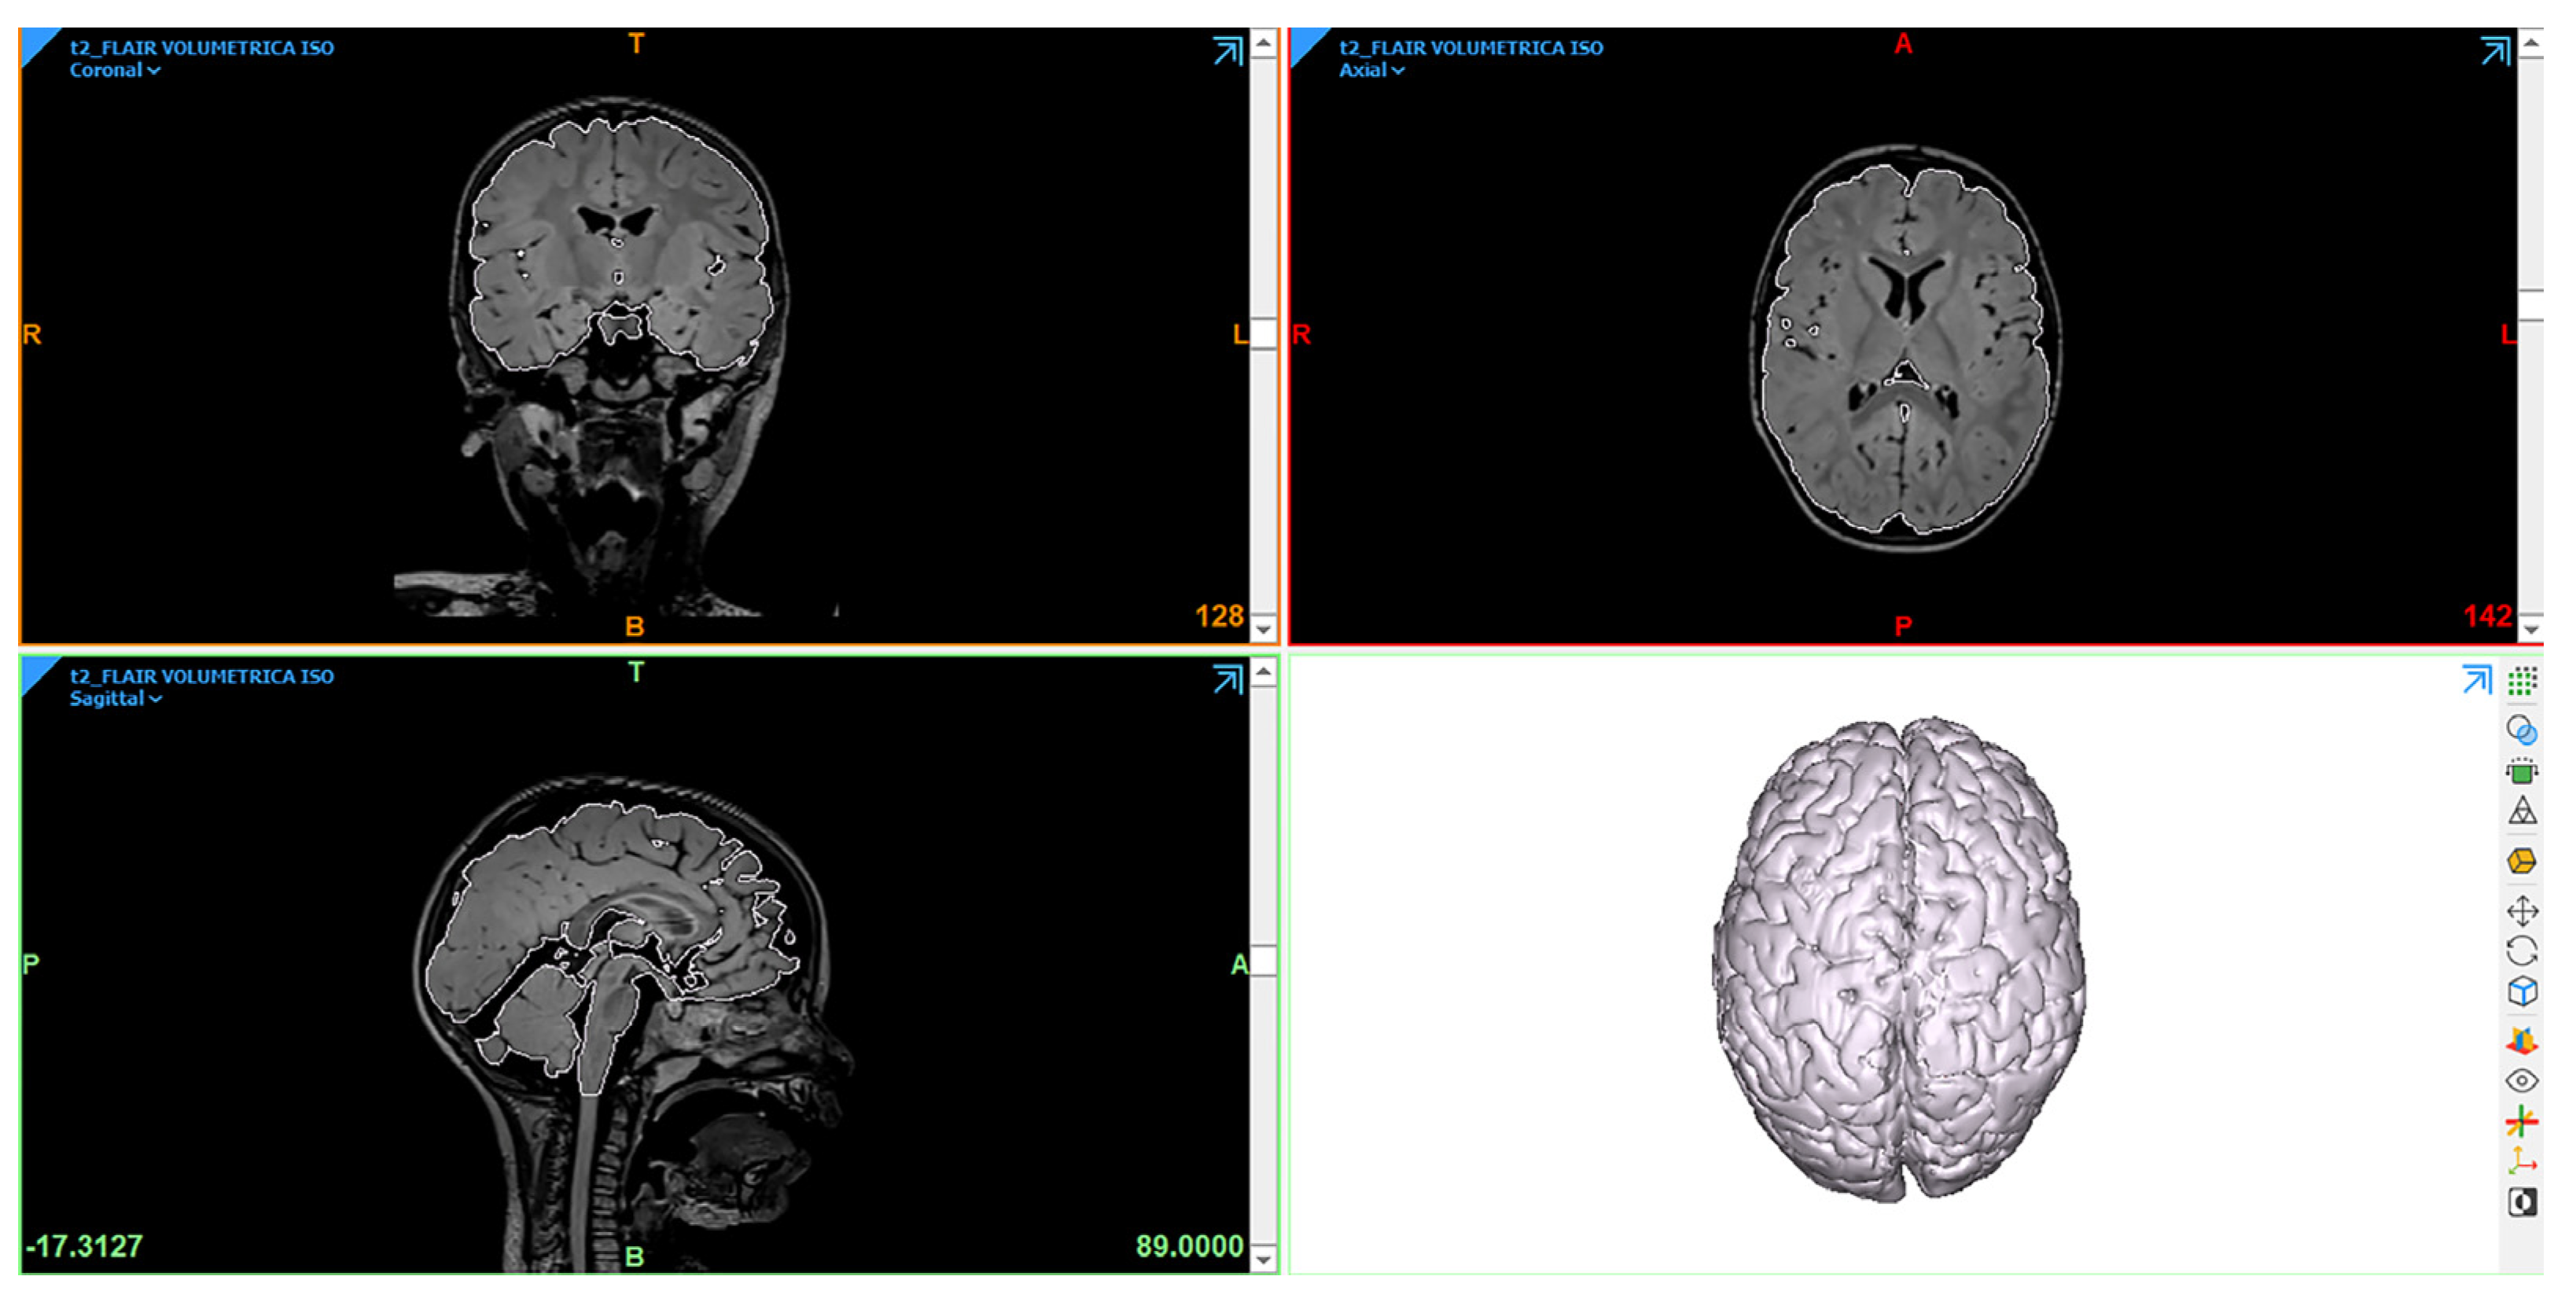

2.2. 3D Modeling

3.1. 3D Modeling